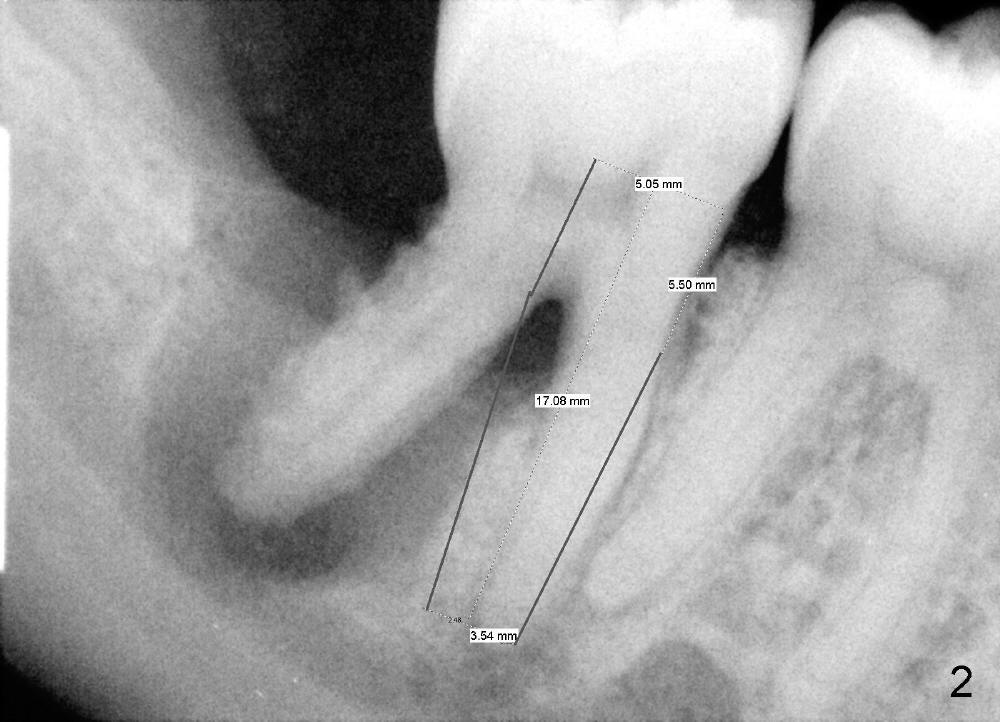

A: after obtaining verbal and written sx consent, Mepivacaine 54 mg, Xylo 34 mg, Septo 68, Epi 34 mcg infiltration, separated gingiva with periotome, pt had pain, Marcaine 9 mg, Xylo 34 mg, Epi 26 mcg infiltration and intraligamental injection, routine ext with forceps, curettage with serrated curette, lot of granulation tissue, until the bottom of the socket, close to presumptive inferior alveolar canal, tissue apparently running mesiodistally, easily removed without active hemorrhage, distal root has abundant calculus, distal socket apparently too large for implantation, copious irrigation, placed Clindamycin gauze x3, mesial socket flat (B-L width is much bigger than M-L one), inserted D1,2 spreader and D2 socket formers with difficulty, handles contact #30 distal crown, inserted RT 2,3,4 and tapered osteotomes 5x18 and 6x18 mm, trying to move the septum distally with much help, inserted 4.5x20 mm tap at 17 mm depth, stable, PA taken: tap close to #30 distal root, approaching IAN (Fig.3), changed to 5x17 tap at 14 mm without stability, when 6x17 tam is inserted at 14 mm, it is stable, PA taken: tap very close to #30 distal root (Fig.4), removed the tap (mesial wall of the mesial socket: no obvious perforation with distal root of #30) and droppd it  into in the distal socket, PA: tap tip overlaps IAN canal (Fig.5), discussed possible nerve injury and touching neighboring root, pt agreed to abort implant placement and place bone graft. placed collagen plug (CollaForm-Plug, Absorbable Collagen Wound DRef CFP1020_5, Lot CFP1020_1301)) in the bottom of the socket (to make room for nerve regeneration), inserted ~.6 cc CANCELL Oss (Mineralized Cancellous Human Allograft, distributed by Implandent LTD, .850-1 mm, 03-0494763/03-0494749, Product Code 06412201, mixed with .3 mg Osteogen (300-400 micron, Osteoconductive Synthetic Bioactive Resorbable Graft, Impladent LTD) into sockets, placed another collagen plug on the top of bone graft, 4-0 chromic gut suture (figure 8 and 1 interrupted), perio dressing, hemostatic. Pt was doing well. POI (oral) and extra gauze given. Continue Amoxicillin, Chlorhexidine, Medrol and Norco, Vitamin B complex recommended